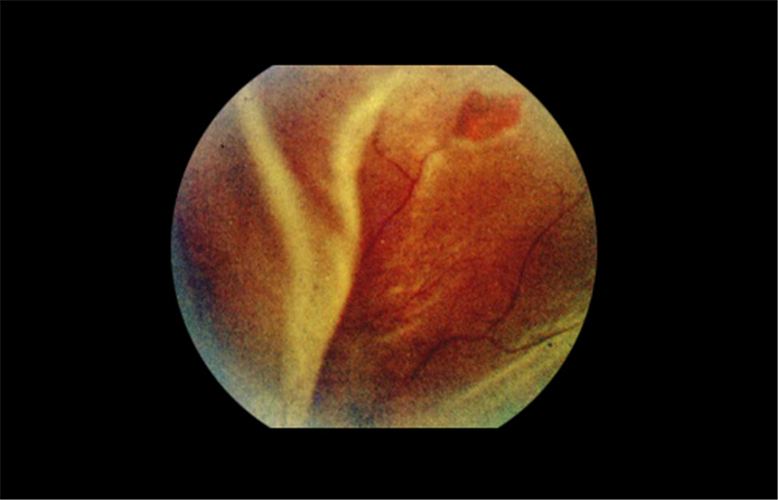

早產兒牽拉性視網膜脫落